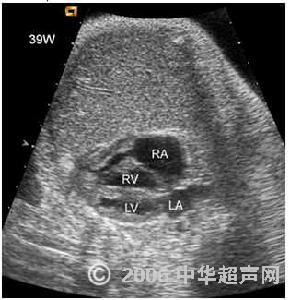

切面超聲心動圖:可直接顯示瓣上狹窄的部位和長度。

(3)切面超聲心動圖:可直接顯示瓣上狹窄的部位和長度。